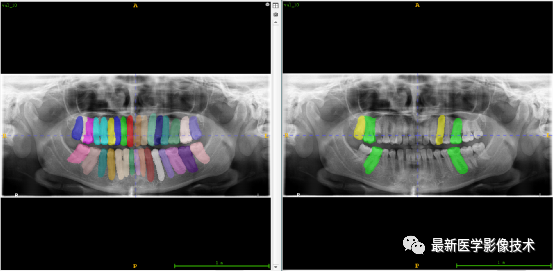

验证集牙齿分割计数和异常牙齿分割识别

左图是分割计数,右图是异常牙齿分割识别结果